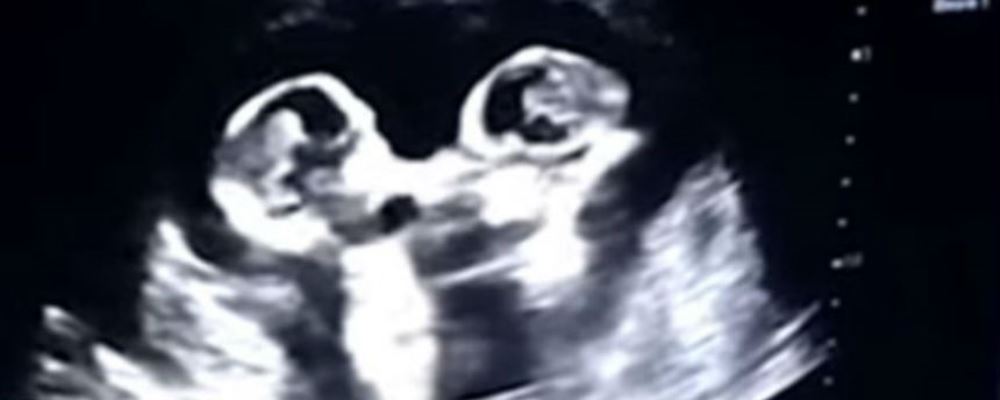

Los bebés suelen dar patadas mientras se encuentran en el útero de la madre, lo que no es ninguna novedad. Pero ahora una ecografía ha captado la tierna «pelea» entre dos gemelas a las que todavía le faltan varias semanas para nacer.

Una embarazada de cuatro meses se realizó una ecografía, en un centro de salud ubicado en la ciudad china de Yinchuan. Todo transcurría con normalidad hasta que su marido, que filmaba el monitor con el que se realizaba el control rutinario, descubrió que -a juzgar por sus movimientos- sus gemelas «parecían estar peleándose».

Tao, el padre de las bebés, explicó al periódico chino The Paper que le parecía muy divertido ver «una pelea de ellas como si estuvieran en un ring de boxeo».